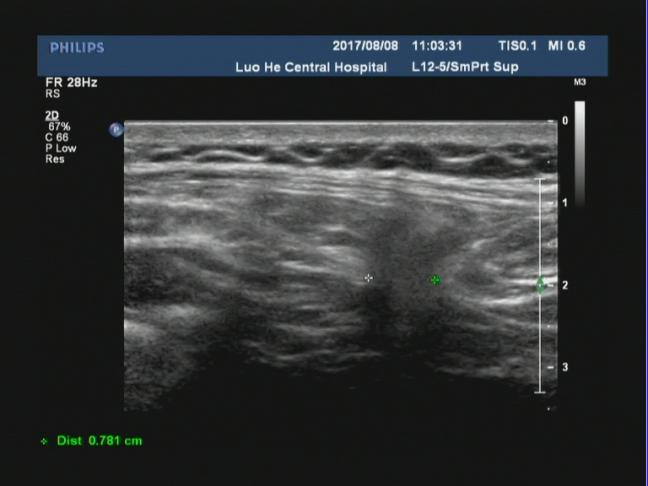

中年男性患者,腹部可见一巨大包块,位于开腹手术瘢痕处,从声像图上可以看出来,该包块直接位于腹部的皮下软组织后方,无肌肉层覆盖,而包块边界处可见肌肉层回声,并且包块内可见腹腔肠管回声,考虑符合腹壁的。

腹壁切口疝指临床体检可触及或影像学检查可显示的原手术切口下的腹壁缺损,是腹部外科手术后的常见并发症,常发生于年老体弱患者可伴或不伴腹壁包块,发病率通常为2%~11%。切口疝无法自愈,可引起患者不适或导致腹腔内容物绞窄。二维超声可直观了解疝环的大小、形态及深度,疝囊大小、位置,疝内容物及疝囊疝出和回纳途径。

对于切口疝二维超声扫描不仅能够清晰显示自皮肤表层到腹壁深层的解剖学全貌,还可直观显示切疝环的大 小、形态及深度,疝囊大小、位置及疝内容物。通过嘱患者用力咳嗽增加腹压或改变体位等方法,超声可实时动态显示疝囊由筋膜缺损处疝出以及回纳的过程。但随着腹壁外科的不断进展和疝修补技术的多样化,外科医师术前需要了解更具体的信息。以往研究认为二维灰阶超声可以检出所有切口疝。但当切口疝的缺损范围较大或存在多发性切口疝时,受小器官探头长度限制,二维灰阶超声存在测量数据明显偏小和病灶检出率明显降低等问题。因此我们可以采用现在新机器上的宽景成像技术,通过连续扫描与拼接图像,不仅可以在同一幅图像上显示较大范围的病灶并进行测量,还可显示周围相邻组织的情况。因此我们要会用、善用新软件,宽景成像不仅可对腹壁切口疝进行容积扫描,明显提高疝气病灶的检出率,客观显示整个切口疝的全貌,准确测量疝囊的大小,为临床医师对切口疝的分类提供准确数据;还可以显示二维超声所不能显示的冠状面图像,更准确地测量疝环,为临床医师选择疝修补术手术方式和决定补片大小提供具体精确的数据。